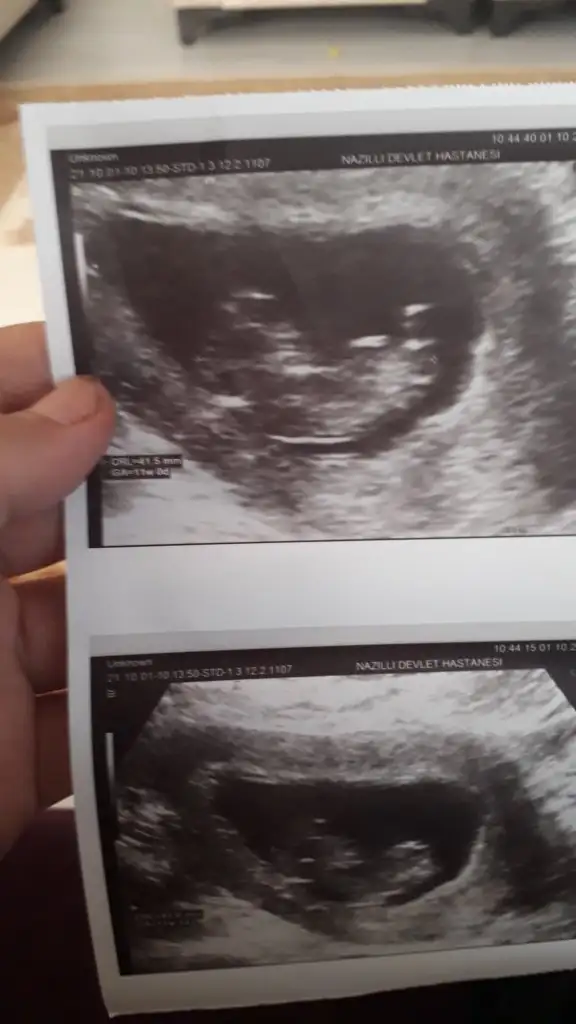

Rica etsem cinsiyet tahmini yapar misiniz